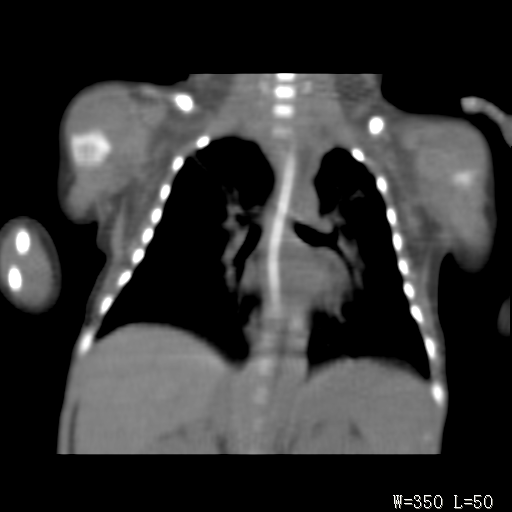

以下是引用改行者在2010-7-8 22:13:00的发言:[br]两肺野透光度降低伴细颗粒状影,两肺下叶见实变影,其内见支气管充气征。 多考虑新生儿肺透明膜病。